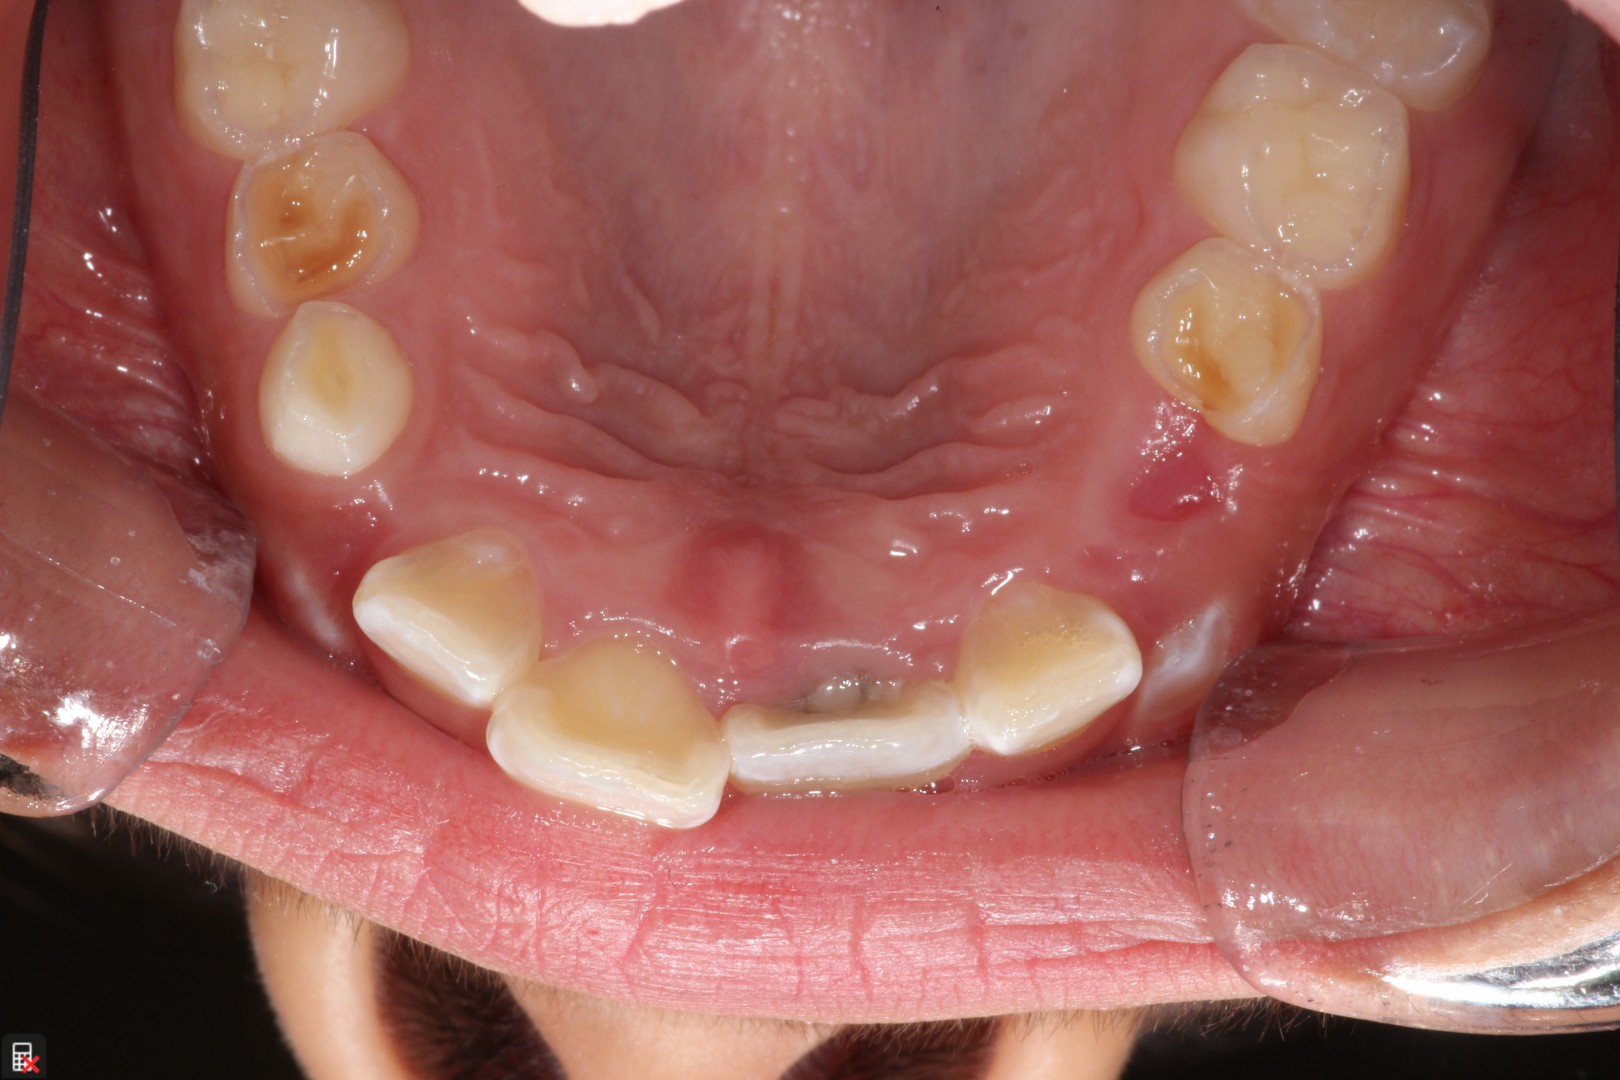

This is a 9yo girl with a high esthetic desire (wants to be a model/actor). She avulsed tooth #9 about 3 years ago, and she has been under treatment with other endodontists. I guess they attempted revascularization with MTA about year ago. #9 is ankylotic with a few mm’s infraposition. It is gray due to the MTA. #8 is slightly yellow/white due to calcification/obliteration but she says she feels cold testing and it is otherwise asymptomatic.